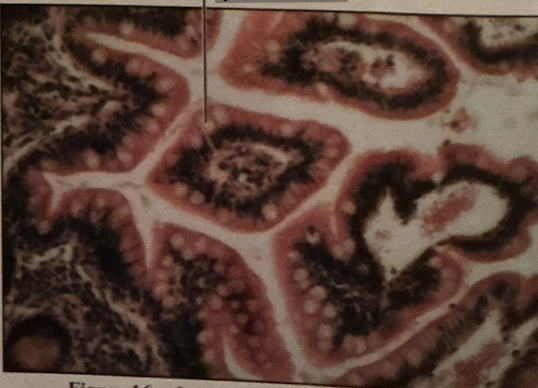

duodenum

jejunum

iluem

duodenum

brunner’s glands

intestinal epithelium

duodenum

________ receives chyme when stomach empties; exocrine release site for gallbladder & pancreatic secretions

intestinal glands

secrete mix of sucrase, maltase, & peptidases + definsins & enzymes

brunner’s glands

produce mucus-rich alkaline secretion to protect from acidic content, lubricate walls, & enable absorption

goblet cells

single-celled exocrine glands secrete mucus

jejunum

ileum

jejunum

mid segment of SI, function in absorption

ileum

last part of SI, absorption of vitamin B12 bound to intrinsic factor

peyer’s patches

lymph tissue in submucosa - end of ileum